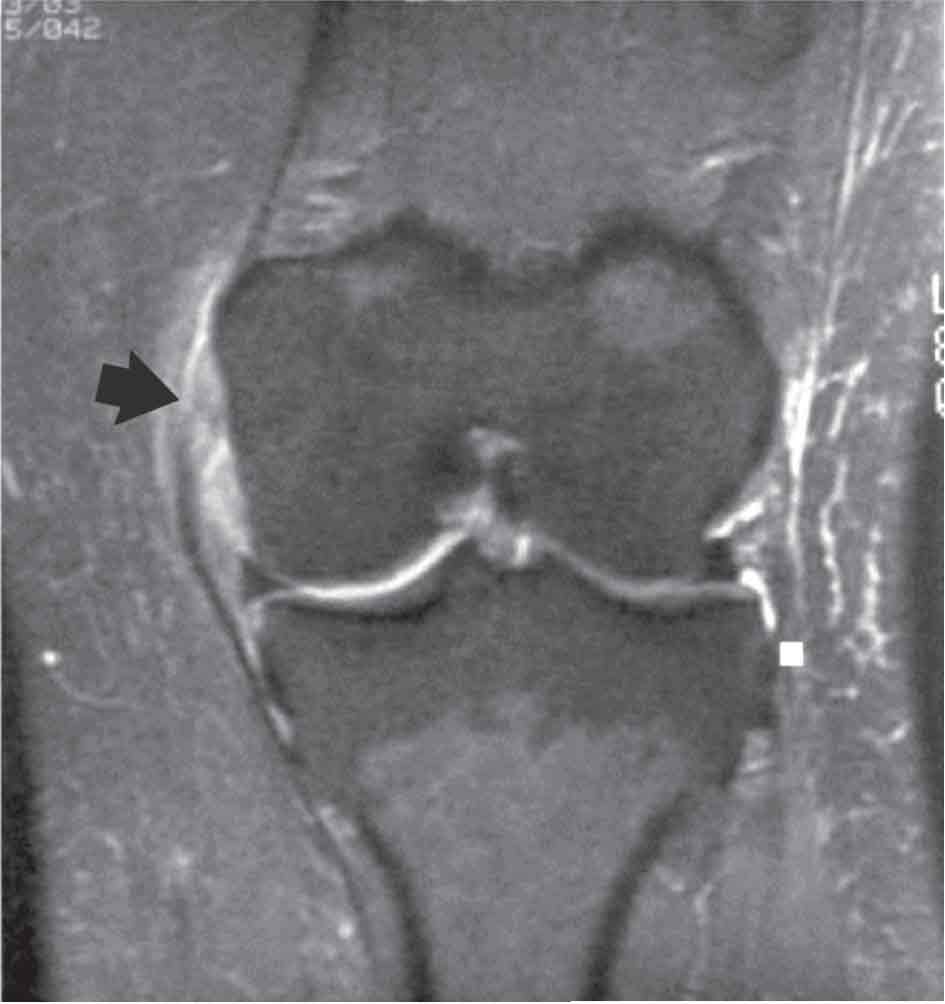

الفحص بالرنين المغنطيسي: هو الفحص الأكثر دقة لتشخيص إصابات الركبة الرباطية، فهو يميز الإصابات التامة من الجزئية، كما يظهر الكدمات العظمية في الجهة المقابلة للإصابة الرباطية، فله لذلك شأن في تحديد آلية الرض المسببة للأذية (الشكل26، 27, 28)

الشكل (26) صورة الركبة بالرنين المغنطيسي تظهر انقطاع الرباط الجانبي الإنسي من مرتكزه الفخذي.